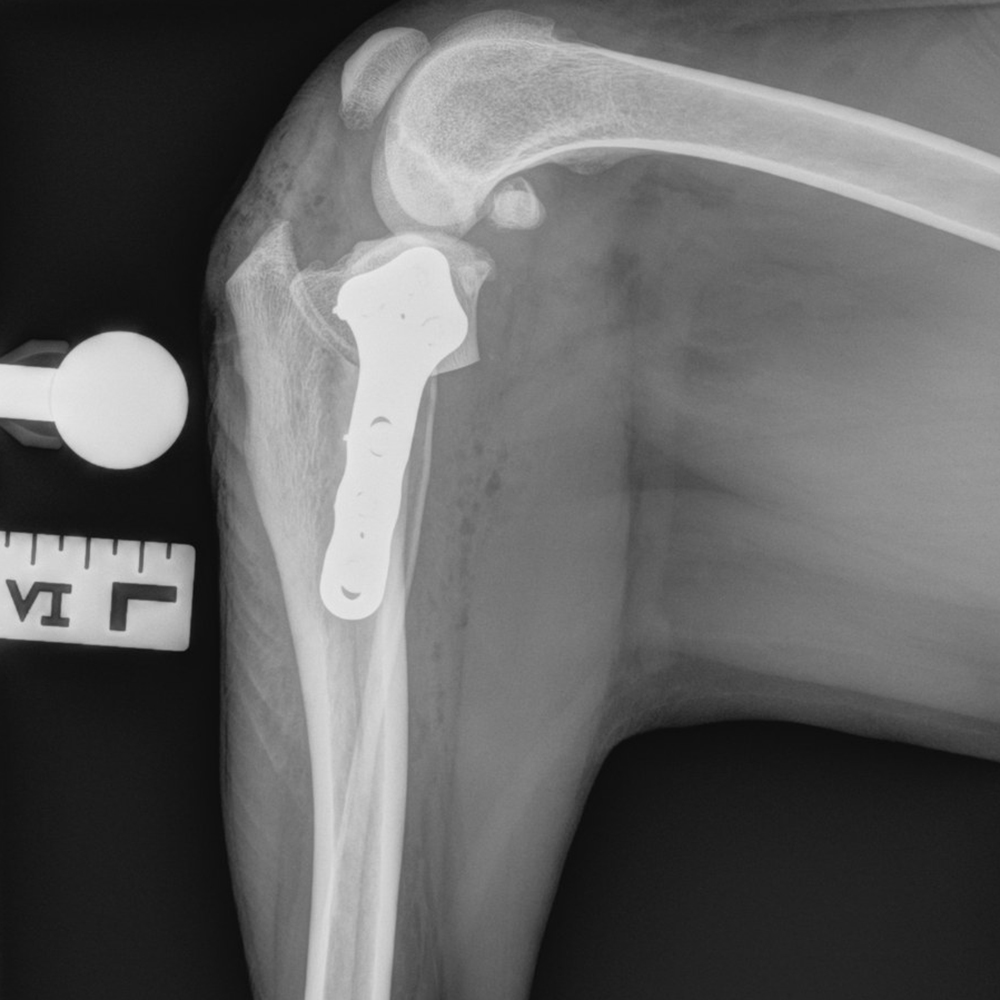

Tibial Plateau Leveling Osteotomy

This course is designed for veterinarians who want to specialize in orthopedic surgery and want to learn advanced techniques for managing knee injuries in small animals.